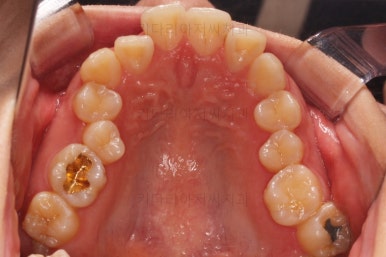

부산무턱교정치과 초진 시 입안의 모습입니다.

전반적으로 치열이 삐뚤고요. 아랫니가 윗니보다 뒤쪽으로 많이 가려져 있죠.

그래서 앞에서 봤을 때 아래 앞니가 거의 보이지 않는 상태인데요.

이런 교합을 "과개교합"이라고 표현합니다.

전반적인 교합, 치열, 과개교합, 튀어나와 보이는 앞니 등을 개선해줘야겠네요.